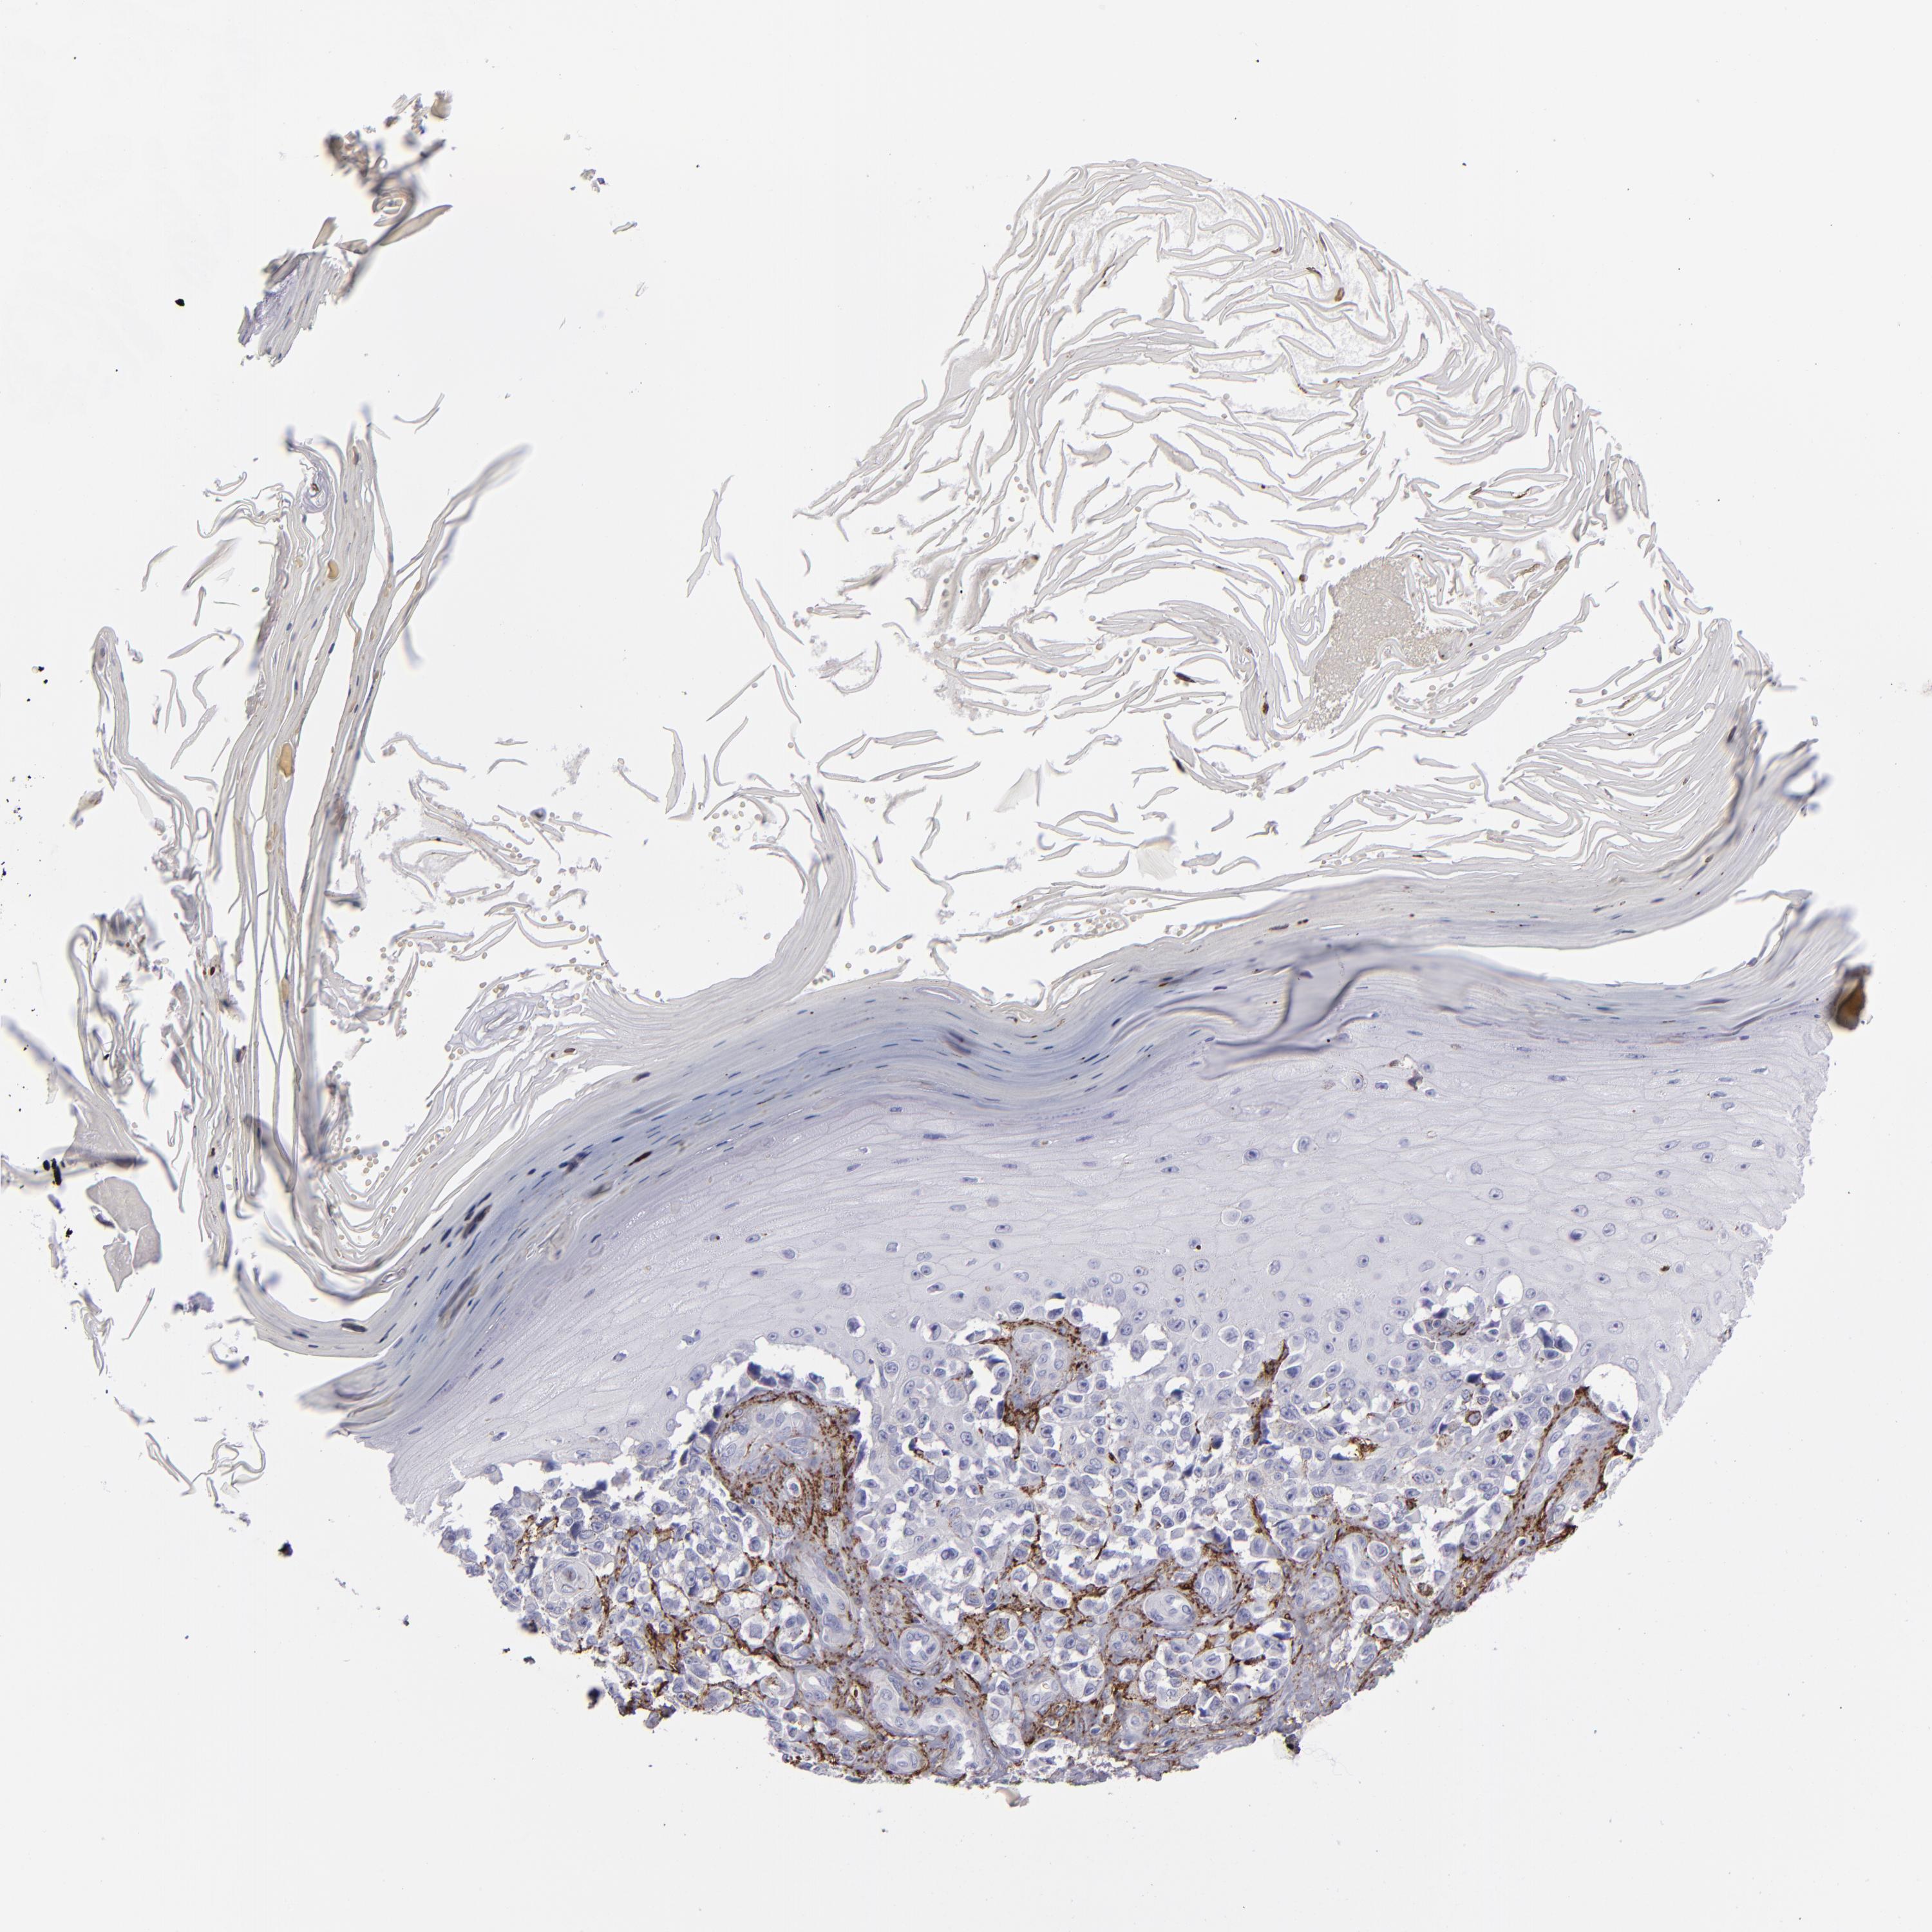

MELANOMA - Protein expressioni

A mouse-over function shows sample information and annotation data. Click on an image to view it in a full screen mode. Samples can be filtered based on level of antibody staining by selecting one or several of the following categories: high, medium, low and not detected. The assay and annotation is described here.

Note that samples used for immunohistochemistry by the Human Protein Atlas do not correspond to samples in the TCGA dataset.

Antibody stainingi

Antibody staining in the annotated cell types in the current human tissue is reported as not detected, low, medium, or high, based on conventional immunohistochemistry profiling in selected tissues. This score is based on the combination of the staining intensity and fraction of stained cells.

Each image is clickable and will lead to virtual microscopy that enables deeper exploration of all samples and also displays staining intensity scores, fraction scores and subcellular localization as well as patient and tissue information for each sample.

Antibody CAB002417

Staining

High

Medium

Low

Not detected

Intensity

Strong

Moderate

Weak

Negative

Quantity

>75%

75%-25%

<25%

None

Location

Nuclear

Cytoplasmic/membranous

Cytoplasmic/membranous,nuclear

Malignant melanoma, NOS